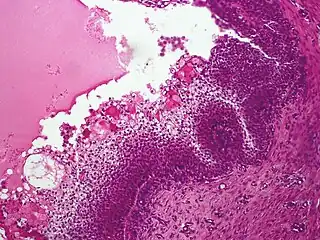

Nodular hidradenoma, showing clear and polygonal cells with foci of eosinophilic material -